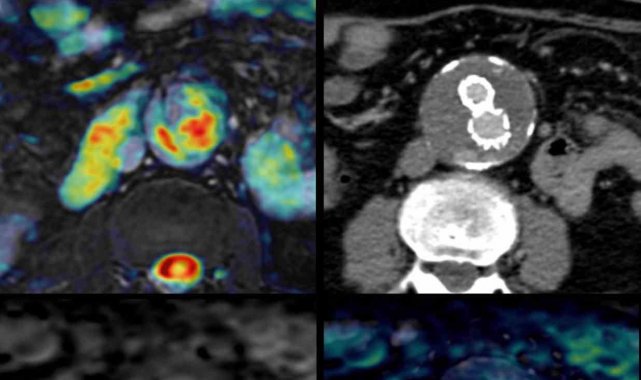

Bir dönem Özel Denizli Tekden Hastanesi'nde de görev yapan Prof. Dr. Nevzat Karabulut'un yaptığı çalışmada; akciğerin bilgisayarlı tomografi anjiyografisi sayesinde toplar damarlardan kaynaklanan pıhtının akciğer damarlarını tıkaması yanında, kalpteki delik nedeniyle kalbin sağ tarafından sol tarafına geçerek ana atardamara ulaştığı ve sol kol damarını tıkadığı gösterildi.

Emboli görüntülemesi konusunda çok sayıda bilimsel çalışması bulunan Prof. Dr. Karabulut, genelde bacak damarlarından kaynaklanan pıhtıların ölümcül olabilen akciğer embolisine yol açması yanında, kalp deliği olan hastalarda ana atardamar yoluyla beyin, kol ve bacak gibi vücudun diğer bölgelerine de geçerek ani damar tıkanmasına (paradoks emboli) bağlı bulgulara yol açtığını belirtti. Prof. Dr. Karabulut'un çalışmasında nedeni bilinmeyen pıhtı atmalarında kalpteki gizli deliklerin mutlaka araştırılması gerektiği vurgulanarak ekokardiyografi ve bilgisayarlı tomografi tetkiklerinin erken ve doğru tanı koymada hayat kurtarıcı rolüne dikkat çekildi.